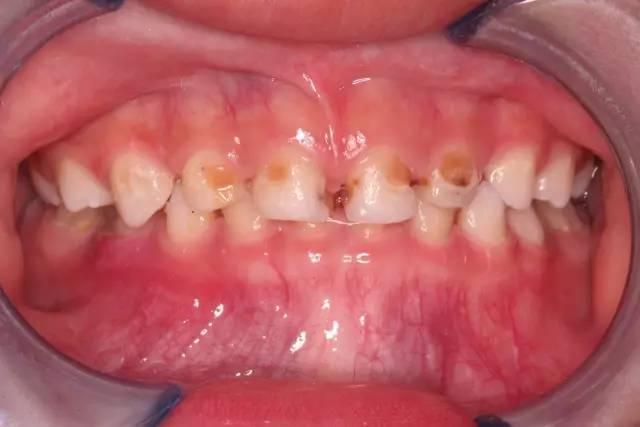

(一)兒童和青少年

乳牙和年輕恒牙的釉質(zhì)礦化程度較低,抗齲能力較弱。

兒童和青少年往往愛吃甜食、零食,且口腔衛(wèi)生習慣尚未完全養(yǎng)成。

據(jù)統(tǒng)計,我國6歲兒童的齲齒患病率高達70.9%。